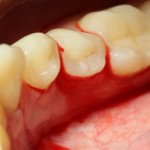

А вот фотография через месяц после операции:

Задайтесь вопросом — оно того стоило? 30 минут в операционной, 4 дня на реабилитацию и 2 недели со швами? Стоило ли это того, чтобы в будущем избежать серьезных проблем со здоровьем?

На мой взгляд — да.